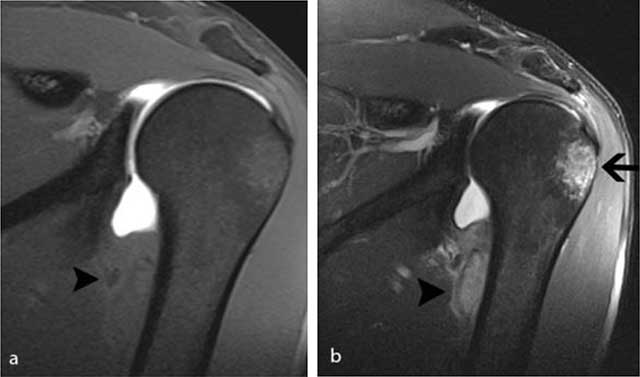

Figure 2

MR arthrography of the left shoulder performed four weeks after initial injury. a) On the coronal FS T1-WI, there is an extra-articular lesion with slightly inhomogeneous signal intensity (black arrowhead) at the medial side of the humeral diaphysis. b) The lesion (black arrowhead) is better seen on the FS T2-WI. Note also the posttraumatic bone marrow edema (black arrow) at the superolateral aspect of the humeral head.

Standard radiography in the acute phase may reveal a small subtle fleck of bone at the periosteal insertion of the teres major. This should not be misinterpreted as a bony Bankart lesion, as the lesion is located slightly more inferiorly. CT may be useful to diagnose a subtle avulsion and for follow-up showing progressive peripheral calcification and ossification and ultimately fusion with the underlying cortex [4]. Although MR (arthrography) is currently a routine imaging tool for evaluation of shoulder trauma in sports trauma, it is important to analyze the images beyond the margin of the joint and scrutinize for extra-articular lesions [8]. Therefore, at least one imaging sequence with a large field of view should be used.